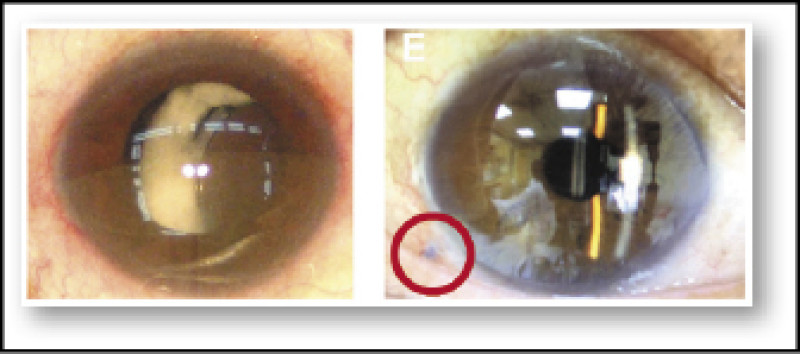

65歲旅居台灣的日籍高階主管,右眼視力「一下子清楚、一下子模糊」,經振興醫院檢查後確診為罕見的「人工水晶體脫位」,因水晶體晃動導致視力不穩,右眼最佳矯正視力僅剩0.4,醫療團隊運用創新的「經鞏膜縫合固定法」進行手術後,他的視力恢復至1.0,且沒有任何併發症。

振興醫院眼科部一般眼科主任許粹剛表示,個案的右眼曾於10年前接受白內障手術,術後恢復良好,隨著時間推移,支撐人工水晶體的懸韌帶逐漸鬆脫,導致人工水晶體脫位,並出現晃動,進而引發視力不穩定。

許粹剛說明,個案採「經鞏膜縫合固定法」,能直接復位原有的人工水晶體,無需更換,手術透過內外縫線穿過眼睛,將水晶體固定在虹膜與前玻璃體腔之間,縫線埋入鞏膜後,利用電燒筆燒灼形成固定點,穩定水晶體位置,此方法縮短縫合和手術時間至約40分鐘,減輕醫師壓力也降低病人恐懼感。